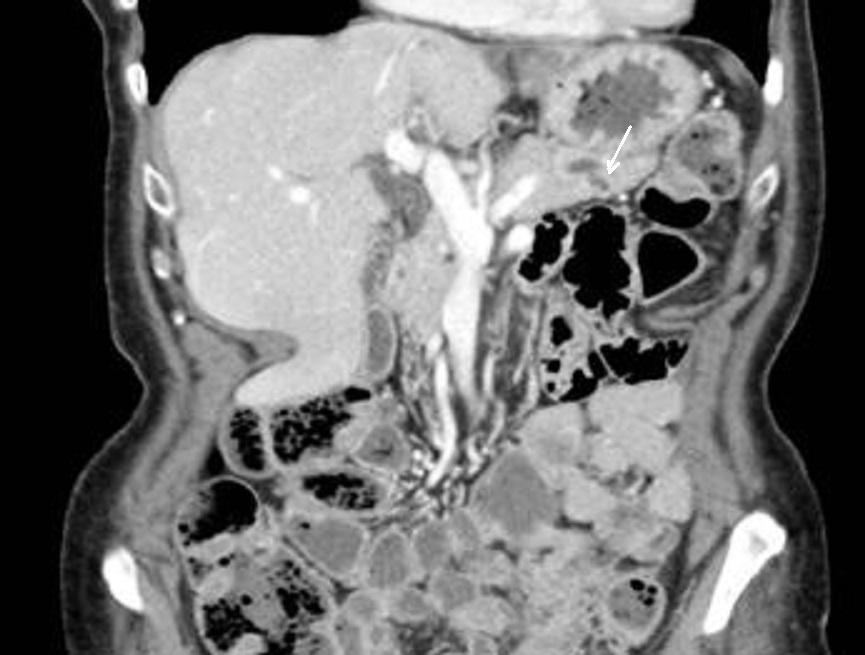

Sus les coupes IRM pondere

sur T2 Image radiolofique des TIPMP de type canaux

secondaire sont des kystes unique ou multiple

arondie ou ovalaire polylobulaire de fortement

hyperintense et comunication souvent avec canal

principale CPP ( fleche rouge ) . Image radiologique

IRM ponderation sur T2 , en coupe axiale |